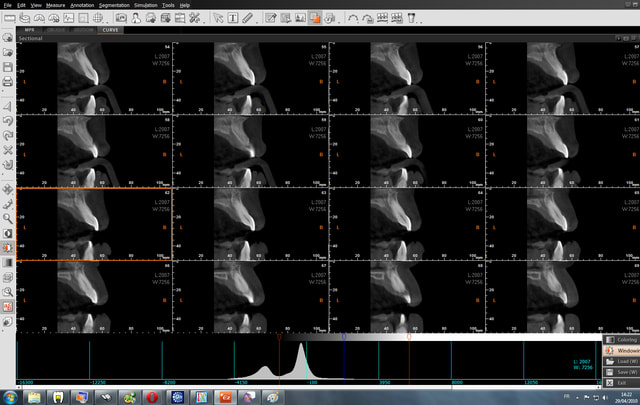

14/12/2009 à 16h13

pour les secteurs molaires

Secteur molaire qo0qll - Eugenol

Emergence sscx71 - Eugenol

Emergence 2 vzpkps - Eugenol

Molaire nldhct - Eugenol